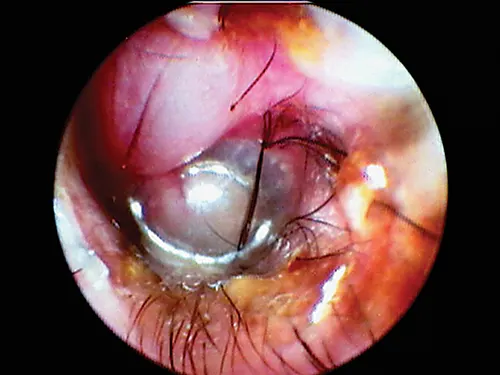

selected slide image

FIGURE 11

1 / 2

Hairs in the horizontal ear canal obstructing the view of the eardrum